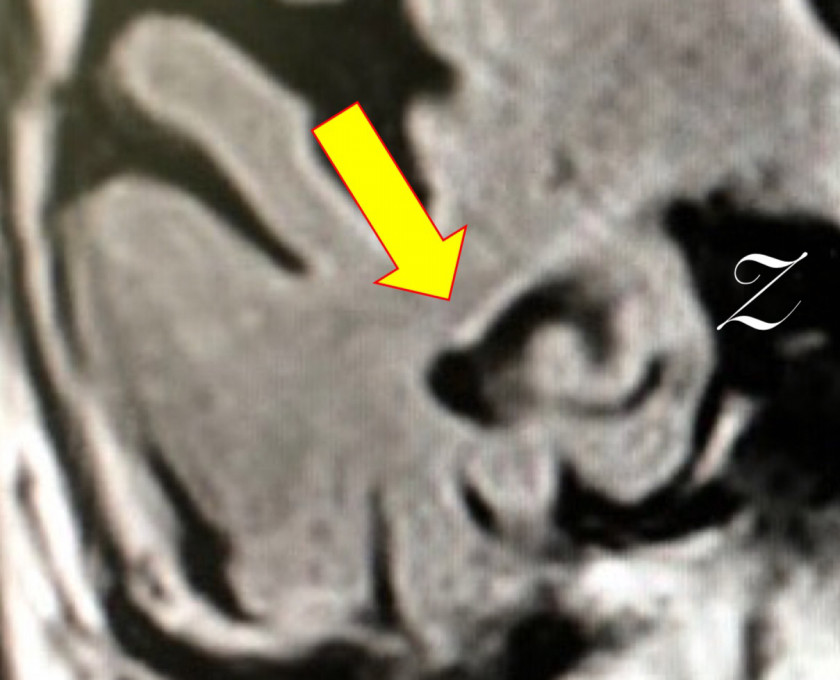

虚血性心疾患の既往もあり。認知機能テストは低得点。MRIも裏付ける内容。他スライスでも明らかな、広汎な白質病変を伴う左右差のある強烈な海馬萎縮。AGDを疑わせるような行動異常は認めず。アルツハイマーにおける海馬萎縮の左右差頻度は拙著に記載した通り、珍しくもなし。年齢的にNFTDとの鑑別は当然だが、過剰リン酸化タウオンリーよりも、アミロイドβ+過剰リン酸化タウのコラボがこの強烈な海馬萎縮の元凶と“妄想”。処方されていたメマリーでノイズを消すことよりも、既往歴と白質病変から考えるに優先すべきことがあるのでは❓

90代前半の症例。風貌は“長身の老紳士”。記憶の問題あり。虚血性心疾患の既往もあり。認知機能テストは低得点。MRIも裏付ける内容。他スライスでも明らかな、広汎な白質病変を伴う左右差のある強烈な海馬萎縮。AGDを疑わせるような行動異常は認めず。アルツハイマーにおける海馬萎縮の左右差頻度は拙著に記載した通り、珍しくもなし。年齢的にNFTDとの鑑別は当然だが、過剰リン酸化タウオンリーよりも、アミロイドβ+過剰リン酸化タウのコラボがこの強烈な海馬萎縮の元凶と“妄想”。処方されていたメマリーでノイズを消すことよりも、既往歴と白質病変から考えるに優先すべきことがあるのでは❓